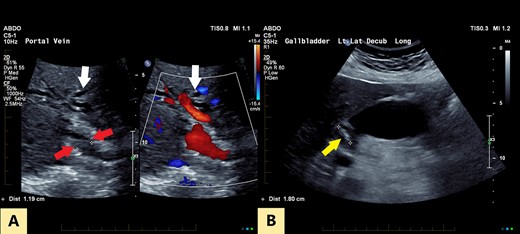

An ultrasound of the abdomen revealed a large gallstone in the gallbladder neck measuring 36 mm with mild biliary dilatation (Fig. 1). Magnetic resonance cholangiopancreatography (MRCP) revealed an irregular long stricture of the extrahepatic bile duct beginning distal to the primary biliary confluence, involving the common hepatic duct for a distance of 20 mm (Fig. 2). A multiphase liver magnetic resonance imaging was performed which confirmed a malignant appearing stricture of the common hepatic duct and showed an ill-defined soft tissue lesion in the porta hepatis between the gallbladder neck and the common hepatic duct (Fig. 3). Her Ca 19.9 was 160 kU/L (ref range < 35 kU/L).

(A) Transverse oblique US reveals segmental wall thickening of the common hepatic duct (between red arrows) with intrahepatic duct dilatation (white arrows). (B) Distended gall bladder with calculus in the neck (yellow arrow).